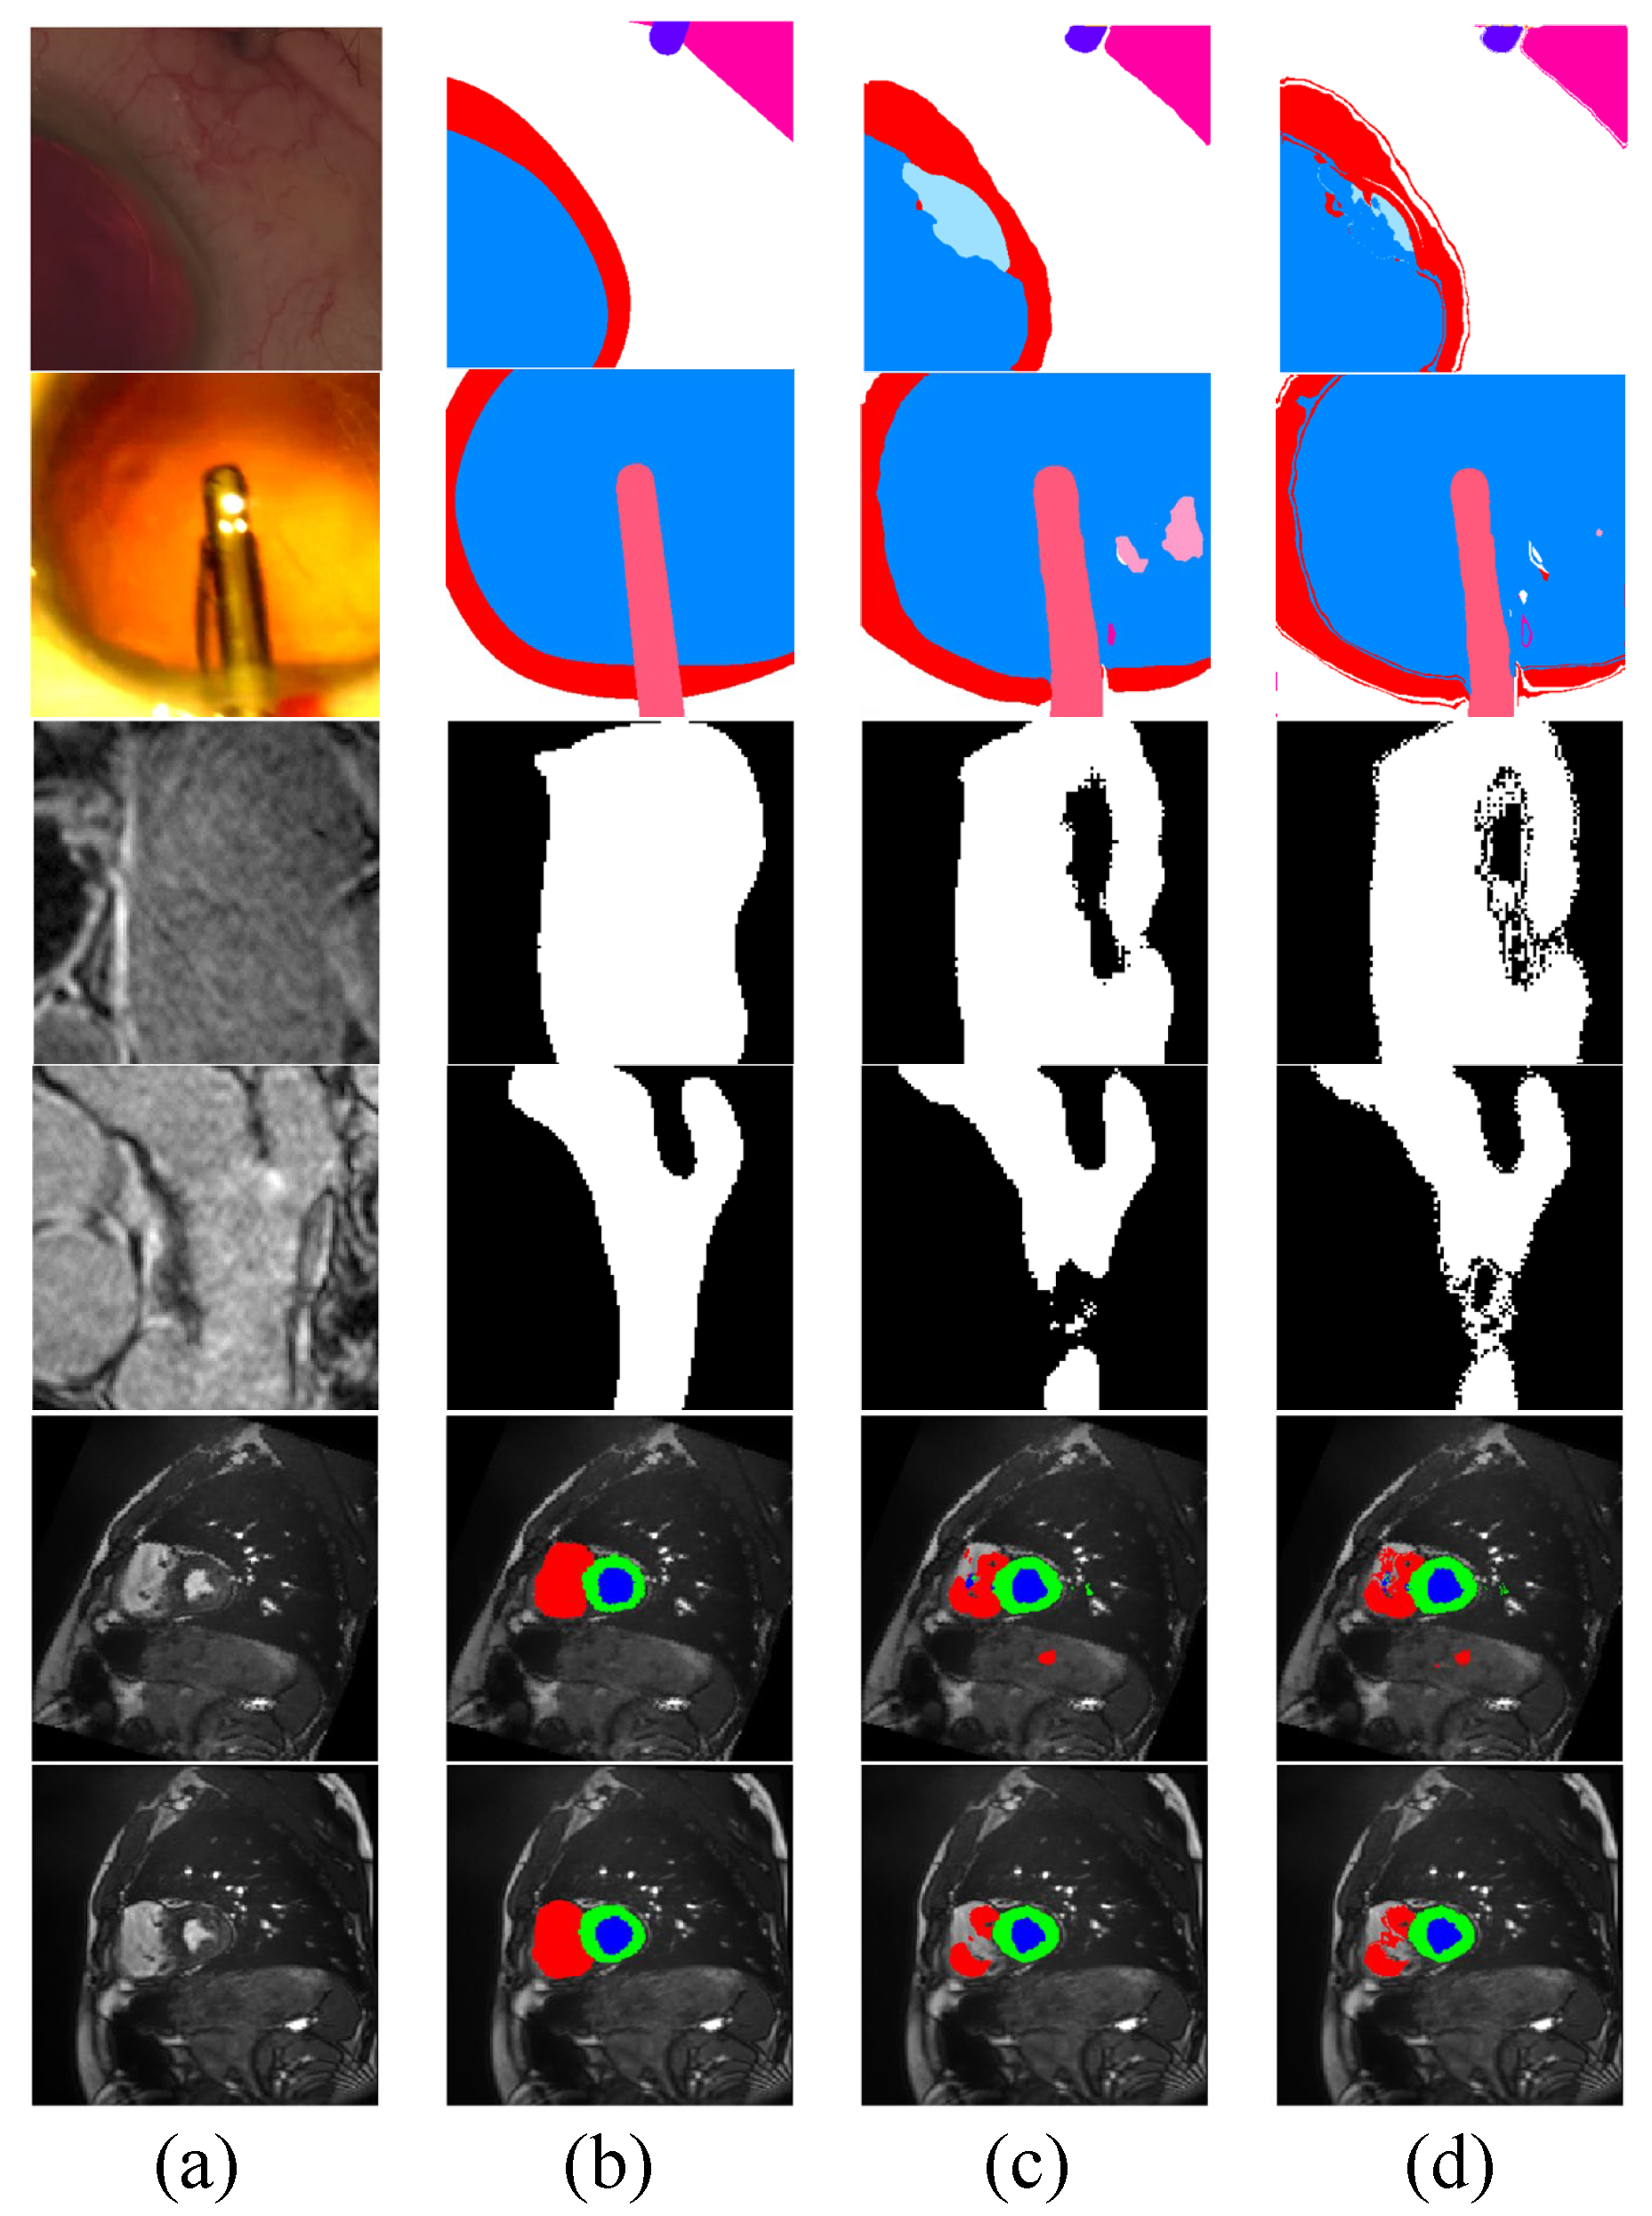

4.2. Results on CaDIS

4.4. Results on ACDC